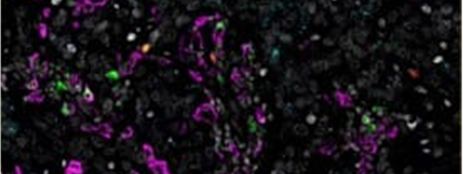

대장암에서 공동 검출로 CD4+ / FOXP3+ regulatory T 세포와 CD8+ / IFNG+ 세포독성 T 림프구를 시각화하였습니다.